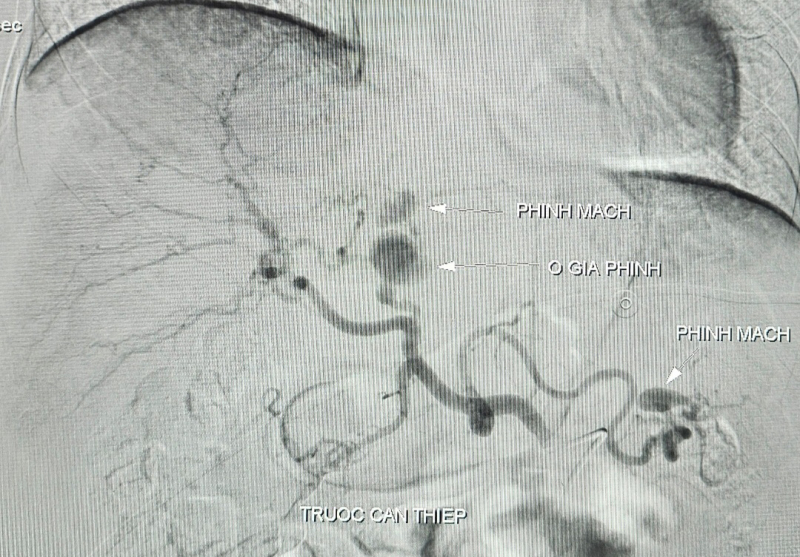

Ngày 10/12, bệnh nhân đột ngột đau bụng vùng thượng vị dữ dội, huyết áp thấp, mạch nhanh nhẹ, niêm nhợt, da xanh (dấu hiệu của mất máu cấp). Bệnh nhân được hồi sức tích cực, bù dịch, bù 6 đơn vị hồng cầu lắng 350 ml cùng nhóm. Kết quả chụp cắt lớp vi tính bụng có cản quang ghi nhận ổ giả phình được cấp máu từ động mạch gan trái kích thước to, tụ máu cạnh bao gan. Bệnh nhân chỉ định can thiệp chụp, nút động mạch các tạng số xóa nền (DSA) với chẩn đoán xuất huyết nội do vỡ phình động mạch gan trái.

Kết quả ghi nhận ổ giả phình động mạch gan trái kích thước 15x22mm kèm phình động mạch gan trái. BS chọn lọc vào nhánh động mạch gan trái có tổn thương, tiến hành thả 3 vòng xoắn kim loại (coils) vào ổ giả phình, bơm hỗn hợp keo sinh học bít hoàn toàn túi phình. Sau 90 phút can thiệp, bệnh nhân ổn định được chuyển khu hậu phẫu theo dõi. Hiện bệnh nhân tỉnh, tiếp xúc tốt, niêm hồng, hết đau bụng, sinh tồn ổn định.